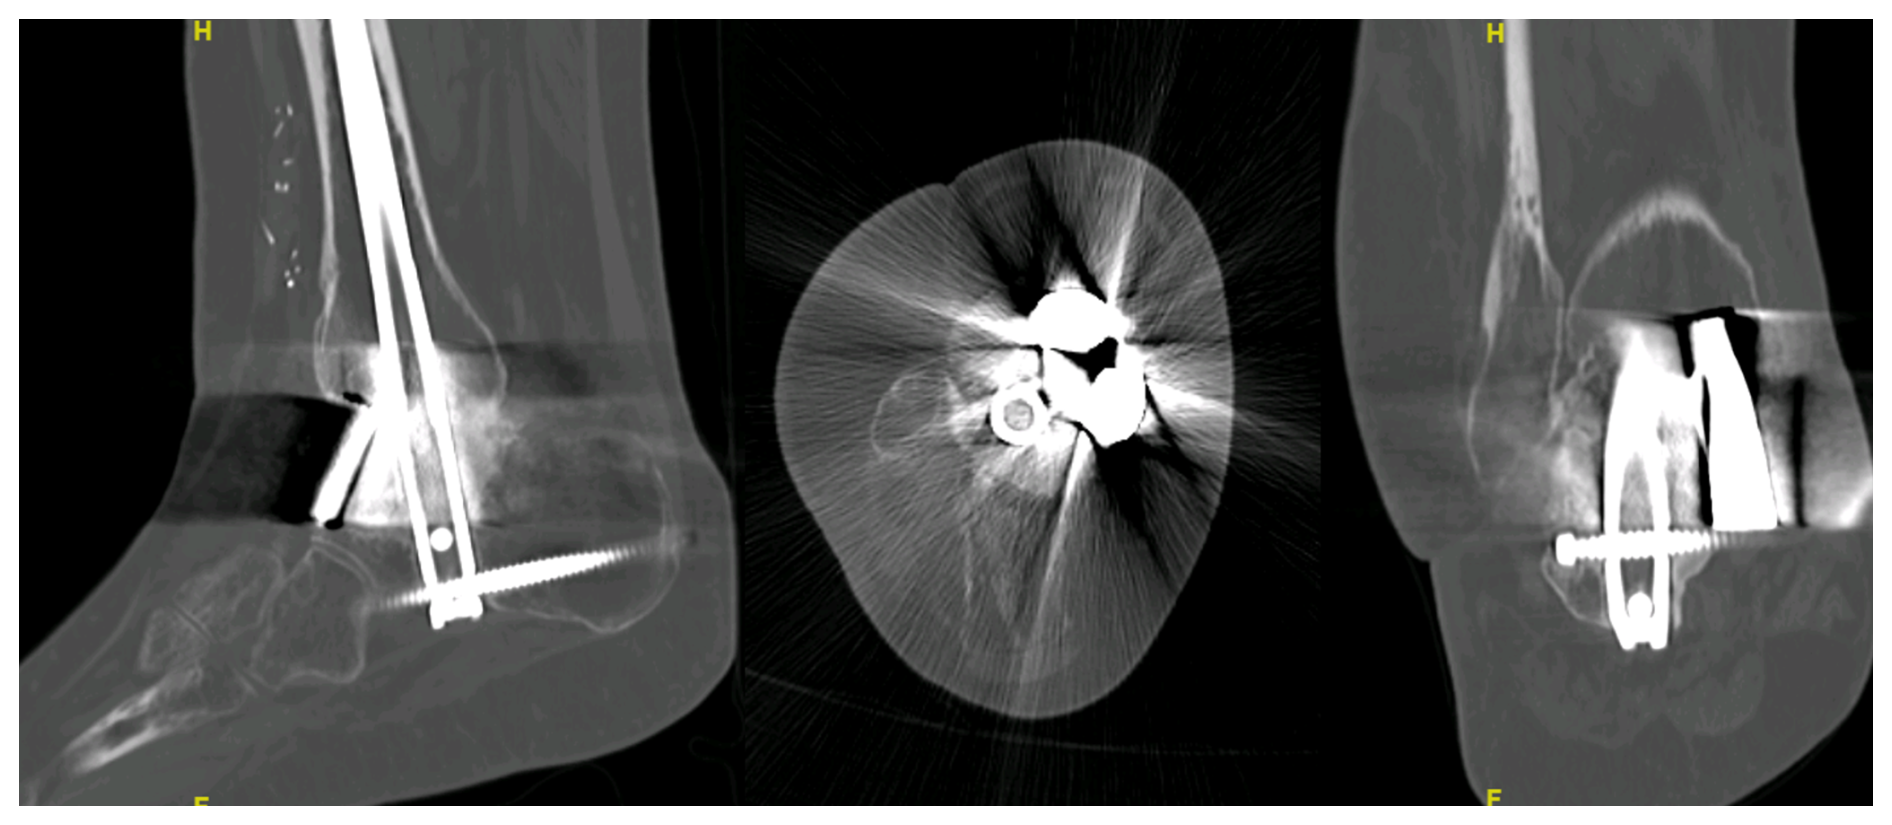

https://jbji.copernicus.org/articles/10/419/2025/jbji-10-419-2025-f04

Figure 4In spite of the image distortion due to radiolucent osteosynthetic material, signs of consolidation and the absence of indirect signs of pseudoarthrosis can be noted in the 1-year control CT scan of one of the patients (Case 2). This image, along with a painless weight-bearing ambulation, is enough to consider a consolidation of the defect.